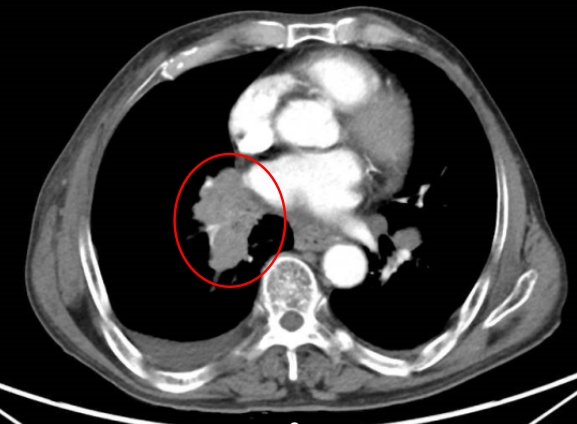

在73岁的王大爷身上,EBUS-TBNA同样发挥了重要作用。患者因胸闷入院,胸部CT显示右肺占位并伴有淋巴结肿大。

诊断结果:小细胞癌

通过对纵隔和肺门淋巴结的活检,EBUS-TBNA能够帮助医生明确癌症的分期,从而指导后续的治疗决策。在活检过程中,医生能够实时观察穿刺针的位置,确保准确性,减少误穿血管的风险。通过获取淋巴结样本,医生能够在不进行侵入性手术的情况下,确认癌症的存在和类型。